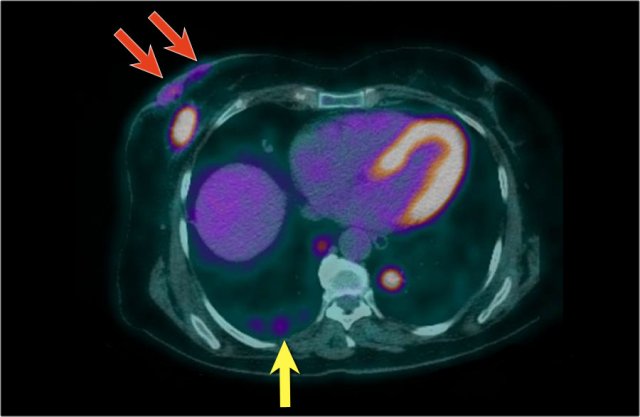

Here another PET-CT example.

On the mammogram, there is a tumor with secondary skin retraction.

Notice multiple linear calcifications within the tumor - click on image to enlarge. This means that the infiltrating tumor developed within an area of ductal carcinoma in situ or DCIS.

Ultrasound demonstrates tumorfoci within the skin, i.e. T4b (red arrow).

On this ultrasound image, there is another satellite nodule within the skin (yellow arrow).

Multiple enlarged axillary nodes are seen (red arrow).

Fine needle aspiration demonstrated metastases within these nodes.

This tumor was staged as T4bN+. This means that we are dealing with locoregionally advanced disease.

These patients are at risk for systemic disease and additional imaging was performed.

Continue...

Here we see the PET-CT image of this patient. Both the breast carcinoma as well as the spread to the skin are demonstrated (red arrows). There are multiple metastases in both lungs - a metastasis in the right lung is indicated by yellow arrow; notice the larger metastasis in the left lung.

In addition, there were also bone- and liver metastases and multiple axillary lymph nodes were seen (not shown on this image).

The cTNM-stage of the tumor is T4bN3M1.